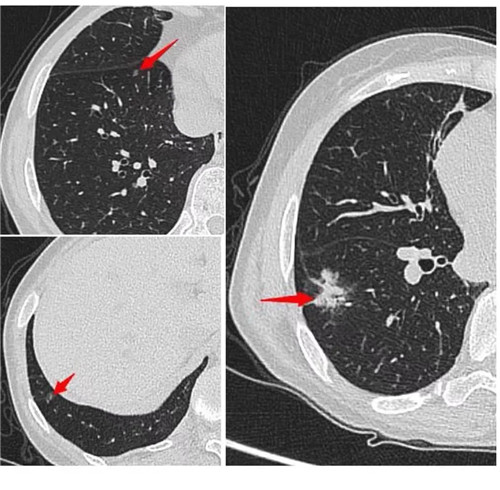

經(jīng)過(guò)術(shù)前充分評(píng)估,崔凱主任決定一次手術(shù)同期為患者切除雙肺總共六枚結(jié)節(jié)。手術(shù)團(tuán)隊(duì)?wèi)?yīng)用minics肺結(jié)節(jié)三維重建分析及術(shù)前CT引導(dǎo)下錨針穿刺定位等先進(jìn)工具,精準(zhǔn)定位患者雙肺的6枚磨玻璃結(jié)節(jié),其中最大的2cm,最小的0.6cm。

術(shù)前各項(xiàng)準(zhǔn)備完畢,崔凱主任為患者行“單孔胸腔鏡右肺下葉切除術(shù) 淋巴結(jié)清掃術(shù) 單孔胸腔鏡左肺上葉尖后段切除術(shù) 左肺下葉背段切除術(shù) 淋巴結(jié)清掃術(shù)”,一次手術(shù)成功將患者兩側(cè)肺部6枚結(jié)節(jié)全部切除,術(shù)后病理結(jié)果提示六枚結(jié)節(jié)均為早期肺癌。